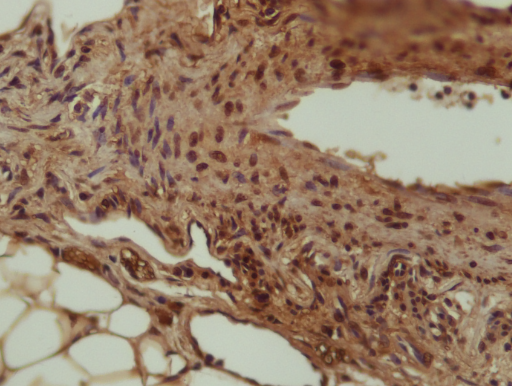

请做过免疫组化的进来鉴定一下我的ICH图片~ 已有5人参与

免疫组化 |